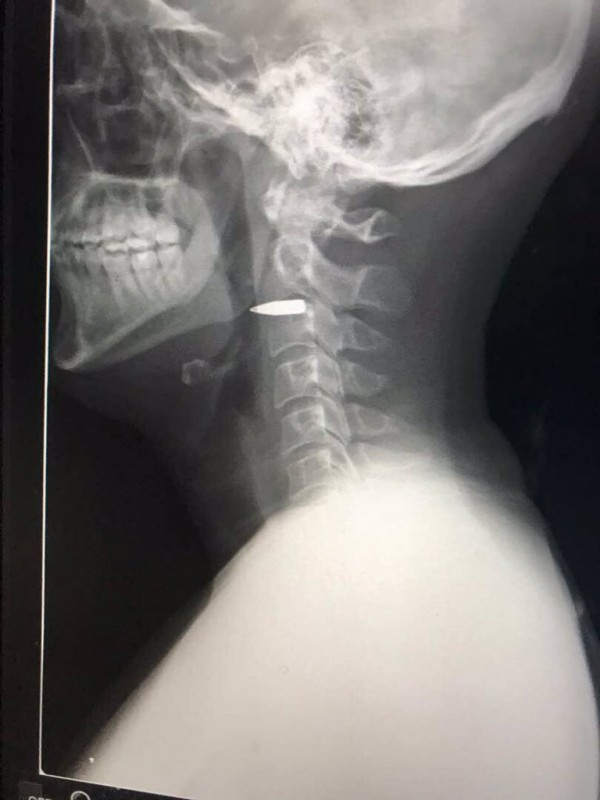

Репортер из Австралии поделился ощущениями от пули в шее Фото: twitter.com/adharves

Когда же ему сделали рентген, стало очевидно, что в его шее застряла пуля. Рентгеновский снимок области шеи журналист опубликовал на своей странице в Twitter. На изображении видно, что пуля прошла между позвонков и, по заверениям репортера, не задела никакие жизненно важные точки.

Репортеру оказали медицинскую помощь, но пулю из его шеи не извлекли.